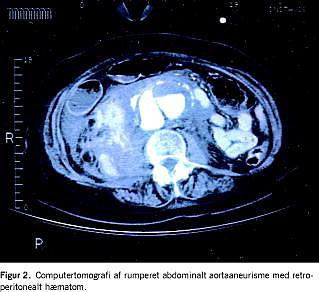

Retrospektiv opgørelse og analyse af mortalitet og morbiditet hos patienter der er opereret for rAAA i 2005 på Rigshospitalet (RH). Morbiditet vurderes ved antal indlæggelses- samt respiratordøgn på Intensiv Terapi Afdeling (ITA), og forekomst af septisk shock og renalt svigt. rAAA er defineret som retroperitonealt hæmatom (Figur 2 ) eller intraperitoneal blødning efter rAAA, der er verificeret ved fund under operation.